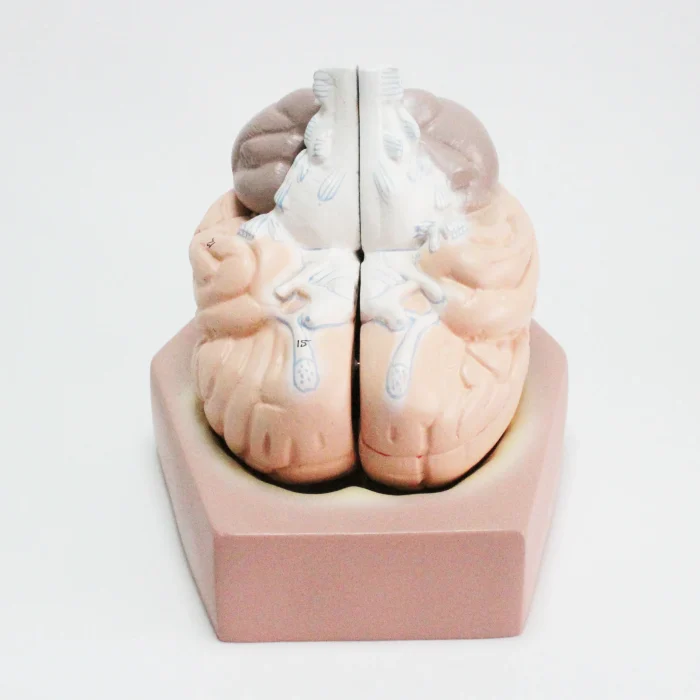

Modèle anatomique de cerveau humain

Modèle de cerveau humain

4 parties : (Fabriqué à partir de fibre de verre)

Modèle anatomique de cerveau humain

4 parties : (Fabriqué à partir de fibre de verre)

Ce cerveau est médialement divisé en deux parties, la moitié droite peut être démontée en frontal avec les lobes parentaux, le tronc cérébral avec les lobes temporaux et occipitaux en deux parties. Placé sur une base amovible avec Key Card numérotée.